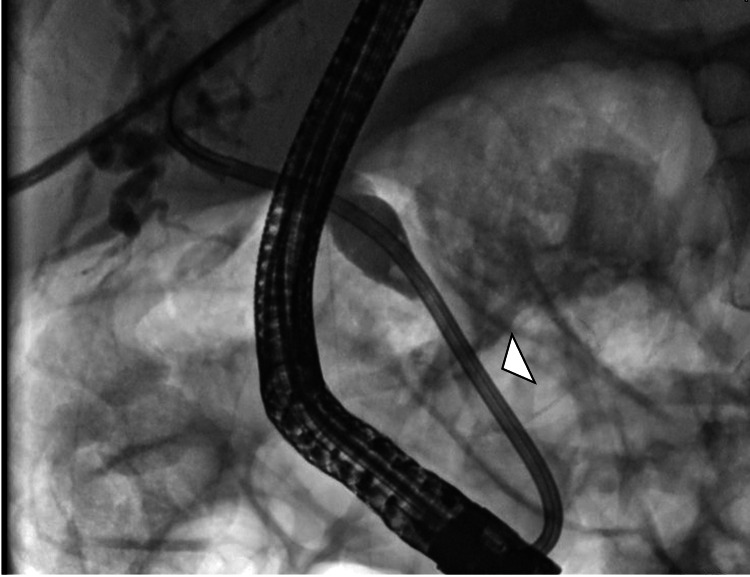

Given the clinical and imaging findings, a diagnostic and therapeutic ERCP was indicated, demonstrating a distal CBD stricture; a 10 Fr × 12 cm biliary stent was placed (Figures 4, 5).

Biliary brushing cytology was negative for malignancy (WHO category II), showing reactive atypia without dysplasia or malignant cells, and PCR testing for Cryptosporidium, CMV, and MAC from bile samples was also negative, supporting pathogen exclusion.